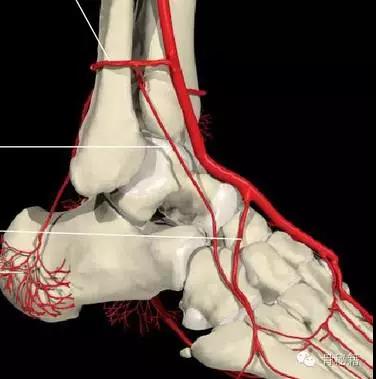

还有一个就是血供的影响距骨很容易坏死就是血供遭到了破坏

相关7个血管:内踝前动脉、胫后动脉、内踝支、跟骨支跗内侧动脉、跖内侧动脉、跖外侧动脉

最主要的血供包括前方胫前动脉内侧胫后动脉外侧腓动脉的分支(跗骨窦)

当发生骨折脱位时,由于位移巨大,导致相应位移的血管损伤、最终导致距骨坏死所以距骨骨折的分型常用Hawkins分型距骨坏死率随分型严重程度逐渐增加